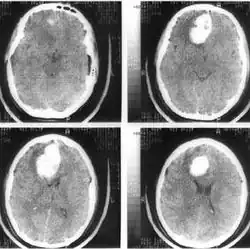

Компьютерная томография головного мозга. Гипертензионная субкортикальная гематома в правой лобной доле

Компьютерная томография головного мозга того же больного через 4 дня после операции — удаления внутримозговой гематомы правой лобной доли